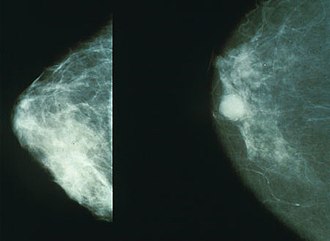

Mammograms - left: non-cancerous; right: cancerous. (WC/NIH)